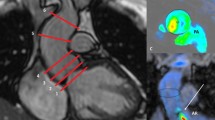

4DF analyses were performed using cloud-based software (Arterys, San Francisco, California, USA). Measurements of aortic and pulmonary artery flow were made at the level of the sinotubular junction for the aorta and midway between the pulmonary valve and pulmonary artery bifurcation, respectively, as per published recommendations [14, 28]. With reference to the 2- and 4-chamber cross-sections, an initial plane was created at end-systole at the mid-leaflet level of the AV valve and orthogonal to flow [16, 27]. Flow was visualized by velocity vectors depicting blood flow directionality in real-time and color-coded for magnitude. Flow through the AV static plane was semi-automatically traced by the software during diastole and manually corrected, as needed. The retrospective valve-tracking AV plane was manually adjusted through diastole to remain near the mid-leaflet level and orthogonal to flow [37], with similar semi-automated tracing of the AV inflow as with the static plane. The regurgitant jet was measured by a plane perpendicular to the jet immediately distal to regions of aliasing, if present [24, 40]. In cases of multiple jets, separate planes were created for each jet and the volume of each jet summed. Care was taken to ensure tracings for each individual jet did not overlap. Time necessary to complete post-processing was recorded for both AIMs and JET.

Our study compares four methodologies calculating regurgitant volume (RVol). Given the clinical utility of regurgitant fraction (RF), we report RF as our outcome. RF was calculated as the quotient of AVVR and AV inflow by the formula RVol/[RVol + semilunar valve net flow (SLNF)]× 100 based on conservation of mass dictating that net inlet and outlet flows are equal. RF was classified as mild (< 30%), moderate (30–39%), moderate-severe (40–49%), or severe (> 50%) [13]. The four methods of calculating RVol were as follows (Figs. 1 and 2; Supplementary videos):

Graphic and mathematical depiction of the indirect methods calculating atrioventricular valve regurgitation (AVVR). a Ventricular stroke volume (SV) is the sum of AVVR and semilunar forward flow (SLFF); b AVVR is derived from the conservation of mass which assumes that atrioventricular net flow (AVNF) equals semilunar net flow (SLNF) in the absence of an intracardiac shunt

In assessing internal consistency, BA and scatter plots comparing all four methods demonstrated narrower limits of agreements and more precise spread of data for the JET method compared to VOL and AIM methods than the VOL method compared to JET and AIM methods (Figs. 3 and 4).

Bland Altman plots comparing the 4 methods in this study: the indirect methods (VOL and both AIMs) and the direct method (JET). The limits of agreements (dashed lines) are narrower for the JET comparisons (c-e) than for the VOL comparisons (a-c). The mean difference is shown as a solid line. Mitral regurgitation (MR) is denoted by red points, tricuspid regurgitation (TR) is denoted by blue points. VOL = volumetry method, AIMstat = annular inflow method by static plane, AIMtrack = annular inflow method by valve-tracking plane, JET = direct measurement of jet